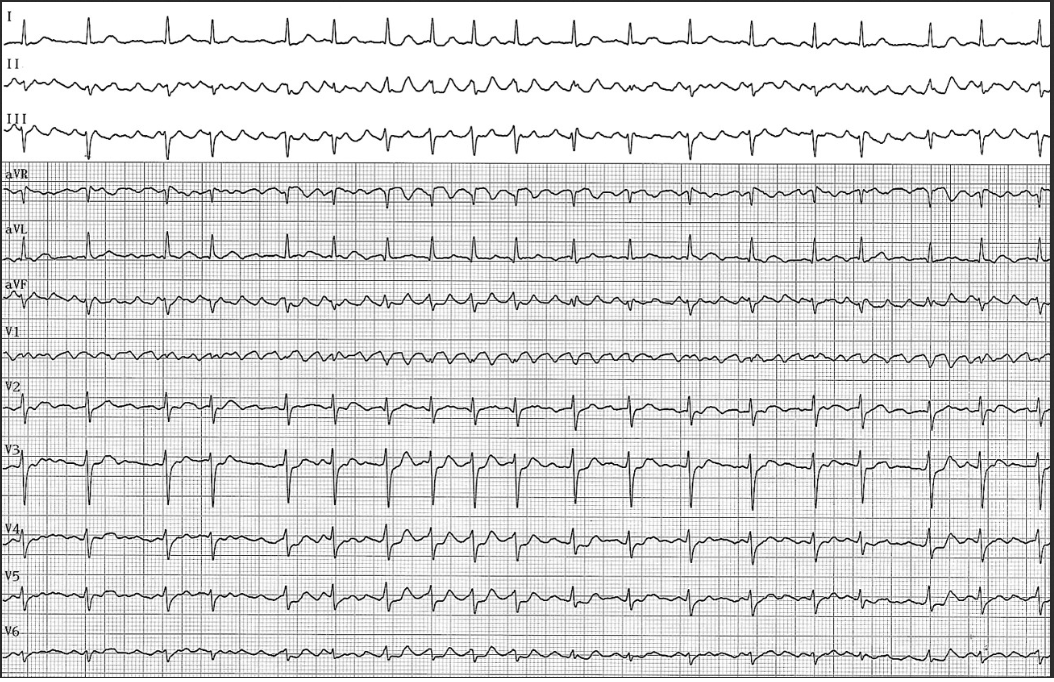

Patiente hypertendue de 54 ans sans autre antécédent. Palpitations depuis 1 mois,On note

A) Une fibrillation auriculaire

B) Un flutter commun

C) Un flutter atypique

D) Un fibrillo-flutter